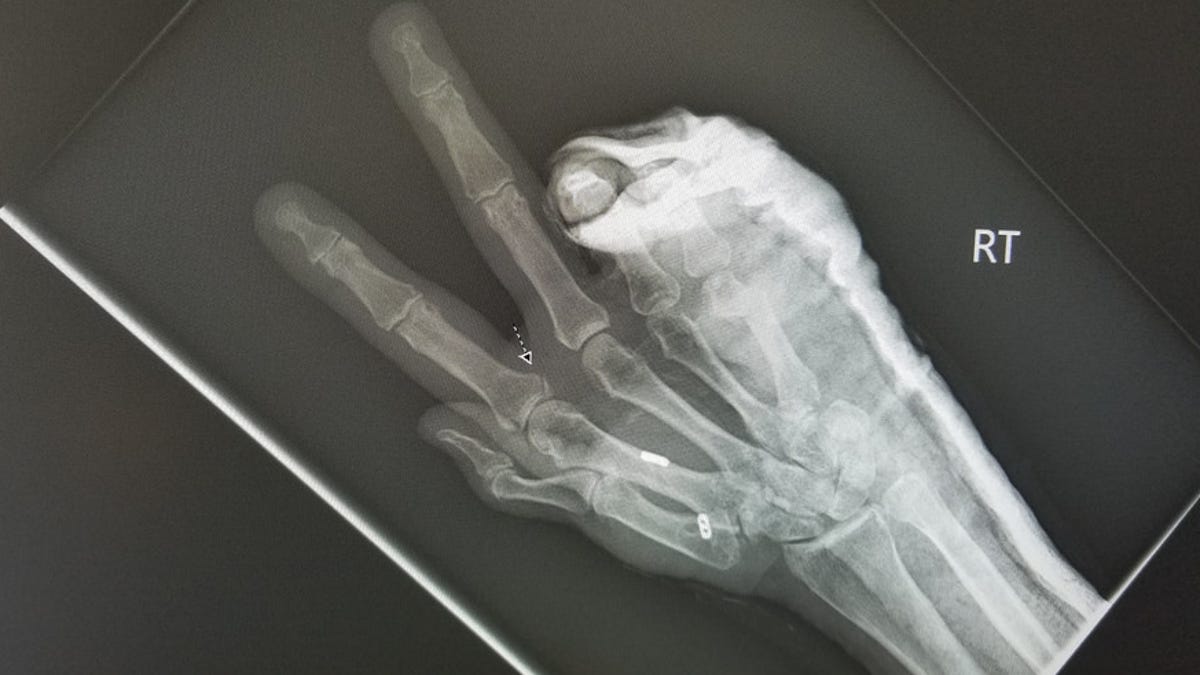

Two surgeries later, Brogan ended up with a broken metacarpal held together with two metal pins in her right hand, along with a cracked knuckle joint, road rash and a hematoma down her entire right leg. Her left hand was so badly swollen, doctors had to cut off her rings.